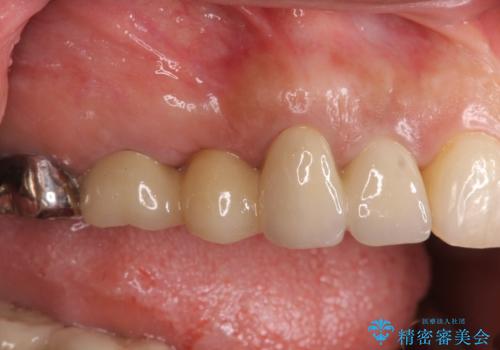

外から見てもなかなかわかりませんが、左側奥歯に大きな虫歯がX線写真で認められるので矯正治療前に虫歯治療を行っていきます。

今回矯正治療に先んじて行われたX 線写真検査により大きな虫歯が見つかり、先に処置を行うことができました。